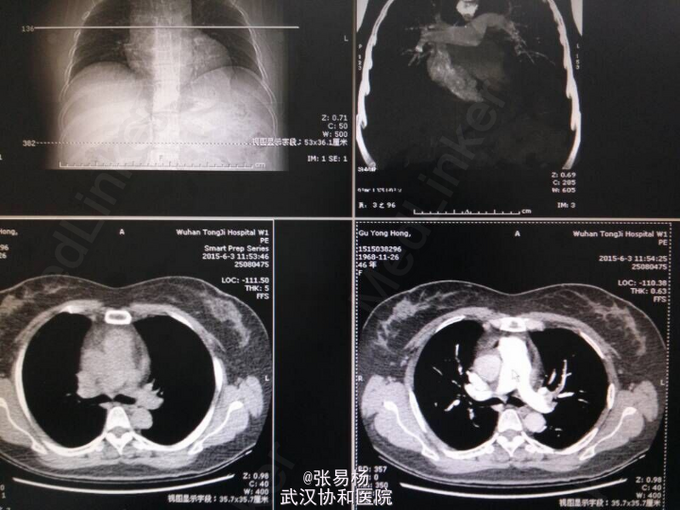

患者,女,47岁 主诉:双下肢胀痛不适10余天 现病史:患者于10余天前无明显诱因出现双下肢肿胀,有轻微压痛,久站及行走后加重,平卧后缓解,余无特殊症状。3天前门诊行双下肢彩超示:双侧小腿肌间静脉血栓形成。 既往有高血压病史3年余,口服利血平片,血压控制可余无特殊。

查体:双下肢水肿,指压征阳性,余无特殊。 辅检:肺动脉血管成像,CT-三维成像示:左肺动脉及其分支,右肺上叶肺动脉及其分支,右肺下叶后段肺动脉充盈缺损,考虑栓塞双肺血管纹理增强,考虑灌注不足所致。